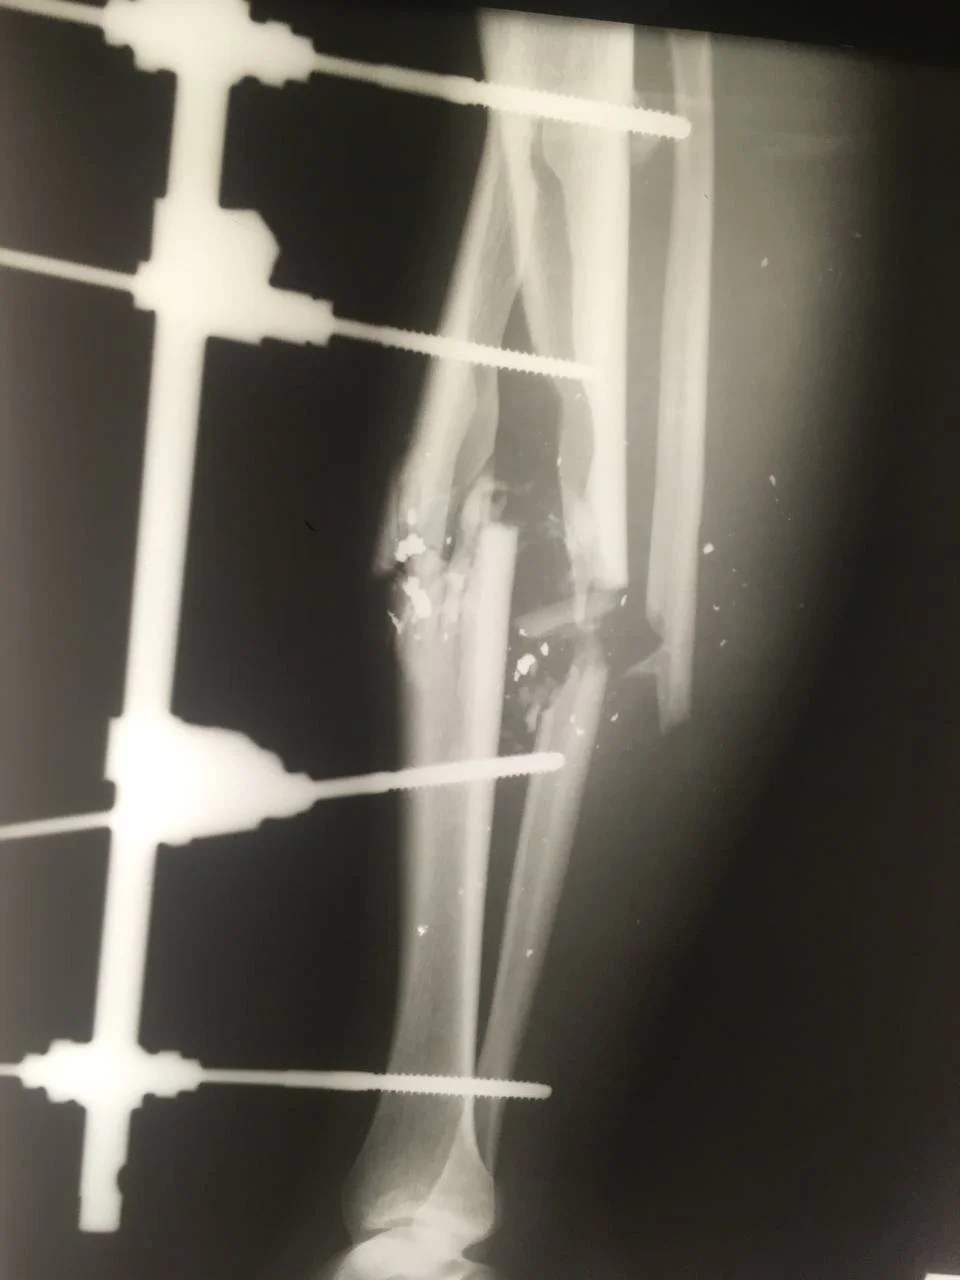

Вот так выглядит нога после осколка. Три секунды на испортить и год на восстановление.

Нога НЕ моя.